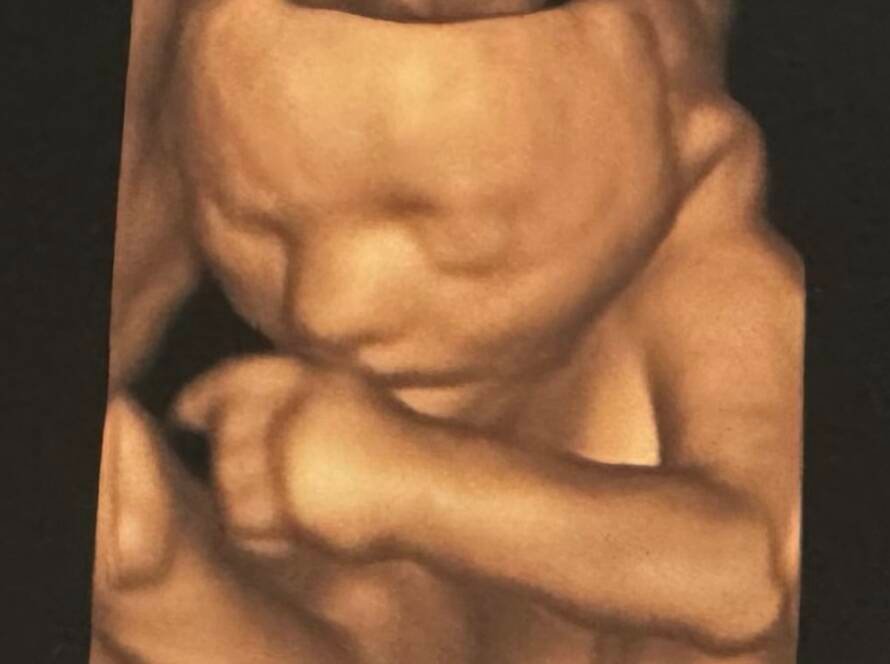

Obstetrik (Gebelik) Ultrasonu Obstetrik ultrason, gebelik süresince anne ve bebeğin sağlığını değerlendirmek amacıyla uygulanan, radyasyon içermeyen, güvenli ve ağrısız bir görüntüleme yöntemidir. Gebeliğin her döneminde farklı amaçlarla yapılan ultrason muayeneleri,…